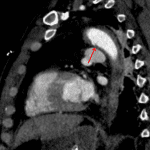

- Acute traumatic aortic intimal tear at the site of attachment of the ligamentum arteriosum with associated focal irregular bulge of the aortic external contour

- Small surrounding mediastinal hematoma

- Acute traumatic aortic injury

Aortic intimal tear at the attachment of the ligamentum arteriosum with a small surrounding mediastinal hematoma and a small focal irregular bulge of the aortic external contour, which is consistent with a small pseudoaneurysm.